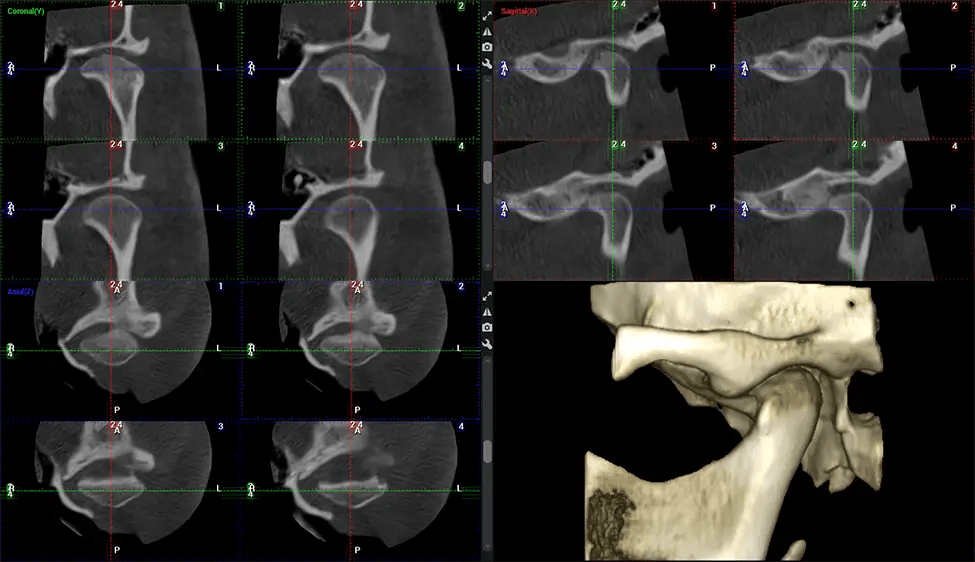

Cone Beam Computed Tomography (CBCT) is an advanced imaging technique used in dentistry and maxillofacial surgery to obtain detailed 3D images of the oral and maxillofacial structures. At Dr G Dental Studio, our CBCT scanners utilize a cone-shaped X-ray beam and a specialized detector to capture images from different angles. A computer then combines these images to create a 3D representation of the patient’s oral anatomy.

This 3D scan, called cone beam computed tomography, gives your dentist a more complete image of your oral anatomy and disease processes than a traditional X-ray. Unlike conventional X-rays, which capture a 2D image of your mouth from various angles, a 3D scan takes multiple digital X-rays for one image. It provides a complete view of your jaw, teeth, nerves, and soft tissues. This enhanced view allows dentists to detect minor issues not visible in traditional 2D scans, such as impacted wisdom teeth or bone fractures in the sinus cavity.

After the scanning process, the captured X-ray images are processed by the CBCT software, which applies algorithms to reconstruct a detailed 3D image of the scanned area. The software compiles these individual X-ray images and creates a digital 3D representation of the patient’s anatomy. The reconstructed 3D CBCT image can be viewed and analyzed by the dentist or radiologist. This image can be manipulated, rotated, and zoomed in or out to examine specific structures and evaluate the patient’s condition.